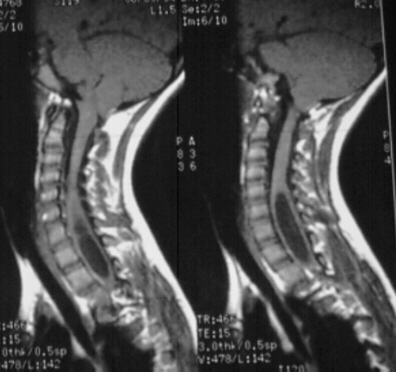

9. A 67-year-old man falls forward from standing height sustaining a hyperextension injury to his neck. He has neurological deficits present on physical examination. A radiograph, CT scan and MRI are seen in Figures A, B and C. Which of the following MOST likely characterizes his neurologic examination?"

FIGURES: A

B

C

DISCUSSION: The patient in the scenario has a central cord syndrome. The images show a relatively kyphotic spine with moderate osteophyte formation from C4 through C6. The MRI shows stenosis without cord signal change. Central cord syndrome is characterized by motor deficits more pronounced in the upper extremities than lower extremities. In addition, finger and wrist motor function is more affected than shoulder and biceps function. Sensory deficits are usually minimal.